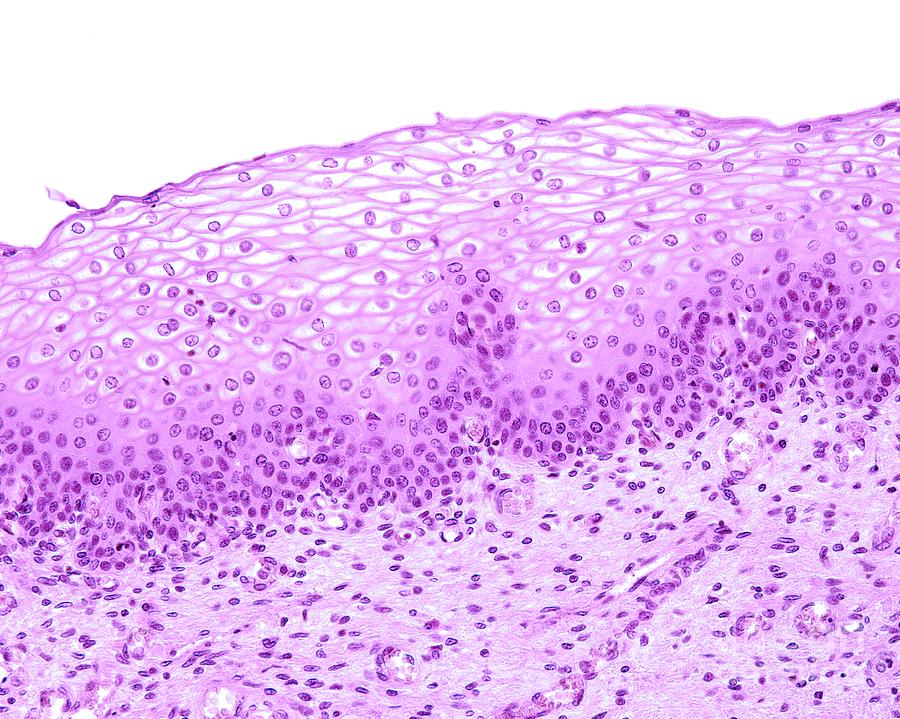

7. What type of epithelium is characterized by being non-keratinised and stratified with three layers?

Explanation

The question asks for the specific type of epithelium that fits the description of being non-keratinised, stratified, and composed of three layers. The correct answer, non-keratinised stratified squamous epithelium, matches these criteria perfectly, making it the right choice. The other three options do not align with the given characteristics, hence they are incorrect.